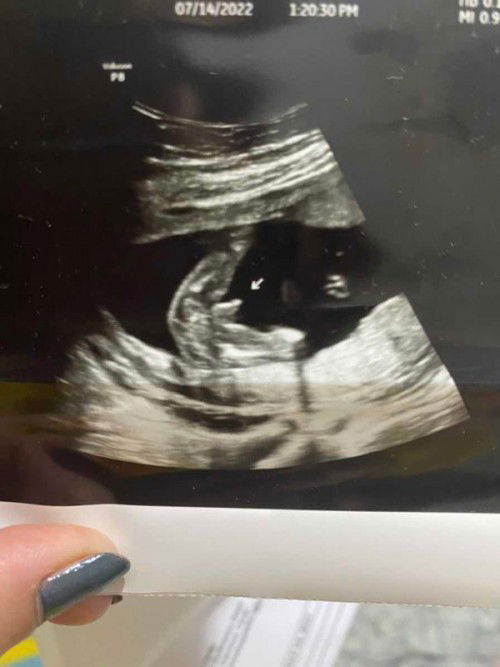

Yung magpapa gender reveal ka sana kso tayong tayo ang pututoy sa ultrasound 🤣 Ang aga naman akong sinurprise ni baby. 🥰 17 weeks only yung ultrasound. #firsttimemom #BabyBoy

Too early pa naman daw po talaga. Nagulat lang din ako nakita na saken. Usually 20 weeks and up po para makita si gender